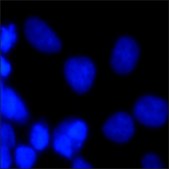

Fluorescent properties of bisBenzimide H 33342:

Free dye: Excitation maximum = 340 nm, Emission maximum = 510 nm (5 mM HEPES, 10 mM NaCl, pH 7.0) DNA complex: Excitation maximum = 355 nm, Emission maximum = 465 nm (5 mM HEPES, 10 mM NaCl, pH 7.0)

Bisbenzimide Hoechst 33342 is a specific stain for AT-rich regions of double-stranded DNA and has been shown to displace several known DNA intercalators. This fluorescent dye has been used in sorting living cells based on DNA content, used in flow cytometry for the determination of DNA content, and for the visualization of chromatin distribution in living cells. It has been used to detect BrdU incorporation into cells and in studying the initial stages apoptosis and cellcycle distribution., Chromosomes that are dividing or replicating will not stain with this dye.

Useful for staining DNA, chromosomes and nuclei. May be used for fluorescence microscopy or flow cytometry.

Excitation max. = 346 nm

Emission max. = 460 nm

Membrane-permeable, fluorescent DNA stains with low cytotoxicity that intercalate in A-T regions of DNA.

Chromatin distribution was visualized in living cells with the selective DNA fluorochrome Hoechst 33342. This dye was shown to be non-toxic on the rat kangaroo PTO cell line by measuring the labelled cell growth rate. The aim of this work